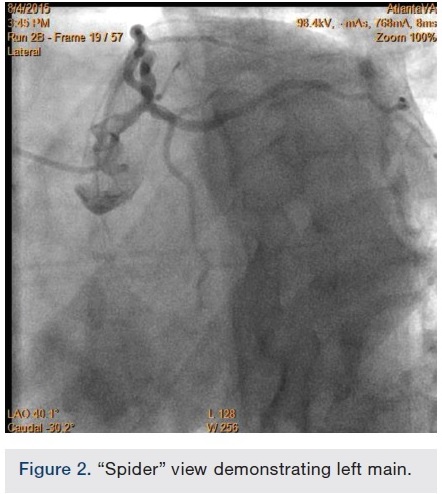

After undertaking initial medical optimization, the patient continued to have extensive symptoms with consumption of 5-6 nitroglycerin tablets (NTGs) on bad days and 2 NTGs on good days. Intravascular ultrasound (IVUS) of the LM was undertaken and this revealed a minimal lumen area (MLA) of 5.0 mm2, consistent with a significant LM stenosis (Figure 4). He was referred for coronary artery bypass grafting, but was felt to be a poor candidate due to his poor left ventricular (LV) systolic function. Therefore, we decided to undertake percutaneous coronary intervention (PCI) of his LAD and/or LM. The overall risk of complications of about 5-6% or so was discussed with patient, including the likely need for hemodynamic support.

In view of the increased complexity of this situation and potentially prolonged procedure times with increased risk of complications, we chose to stage the procedure in two phases: peripheral and coronary. Accordingly, the patient was brought in, the left common femoral artery was accessed using a micropuncture technique, and a 10 cm, 7 French sheath was placed in the artery. Angiography of the left iliofemoral system was performed using a 4 French multipurpose catheter. This was followed by IVUS, revealing a 38.1 mm2 reference segment area and a minimum 8.6 mm2 stenosis area, equating to an 80% area stenosis within the left external iliac artery (Figures 5-6). The wire was exchanged for a 260 cm Rosen wire (Cook Medical) and the lesion was first predilated with a Workhorse II 6 mm balloon (AngioDynamics) at 10 atmospheres for 60 seconds for two successive inflations. The balloon was then removed over the wire and the short 7 French sheath was exchanged over the wire for a 25 cm, 7 French sheath, which was advanced over the Rosen wire into the distal aorta. An 8 mm x 38 mm x 120 mm iCast covered stent (Atrium Medical) was then advanced to the level of the stenosis and unsheathed via retraction of the 7 French long sheath. The stent was deployed at 10 atmospheres for 60 seconds. There was still a small waist in the proximal stent and this was post dilated with the stent balloon at 13 atmospheres for 90 seconds with excellent angiographic result and no evident perforation or dissection, yielding 0% residual stenosis (Figure 7).